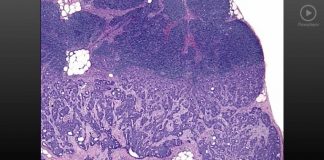

3-5 Tumor Progression

TUMOR PROGRESSIONI. TUMOR INVASION AND SPREAD

A. A ccu m u I at io n of mu t a t ion s eve nt ua...